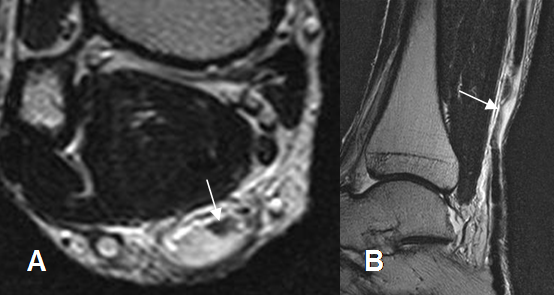

Fig 82. Tendinosis crónica del aquiles.

Ecografía vista axial. Engrosamiento del tendón con alteración de su ecogenicidad, por inflamación crónica.

Fig 83. Tendinosis crónica del aquiles.

A: RM axial en T2. Engrosamiento del tendón, con pérdida de la concavidad anterior.

B: RM sagital en STIR y C: RM sagital en T2. Engrosamiento de la zona crítica del tendón, conservándose la señal.